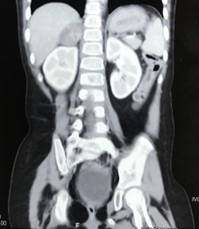

Figure 3: CT Abdomen showing right adrenal mass